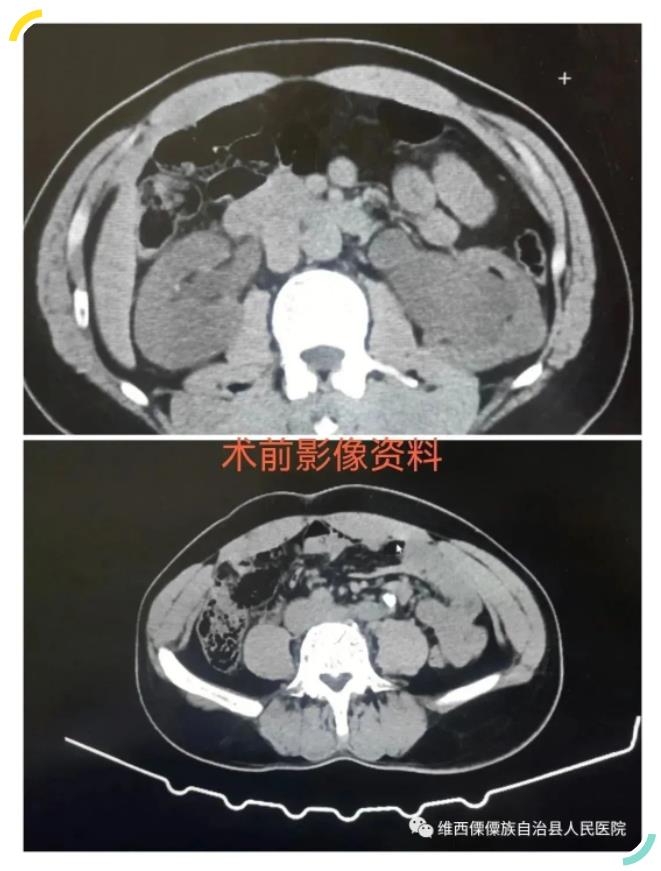

近日患者蜂某,男,45 岁,因“突发右侧腰背部疼痛 3 小时余”到维西县人民医院普外科门诊就诊。门诊医师结合病史、查体后初步考虑“右肾绞痛”,予完善相关检查后诊断“1、右侧输尿管结石伴积水 2、右肾绞痛 3、左侧输尿管结石伴积水”收住入院。

因患者双侧输尿管结石,需急诊行手术治疗解除输尿管梗阻保护肾单位,防止出现急性肾功能衰竭,入院后主治医师积极完善相关检查及准备,术前沟通告知手术目的、方式、风险并签署手术同意书,在麻醉科及相关辅助科室的积极配合下送入手术室,在全麻下右侧输尿管结石行输尿管镜钬激光碎石取石术+输尿管支架置入术,左侧输尿管结石因结石嵌顿时间长,肉芽包裹,予留置输尿管支架解除梗阻,拟二期手术治疗。